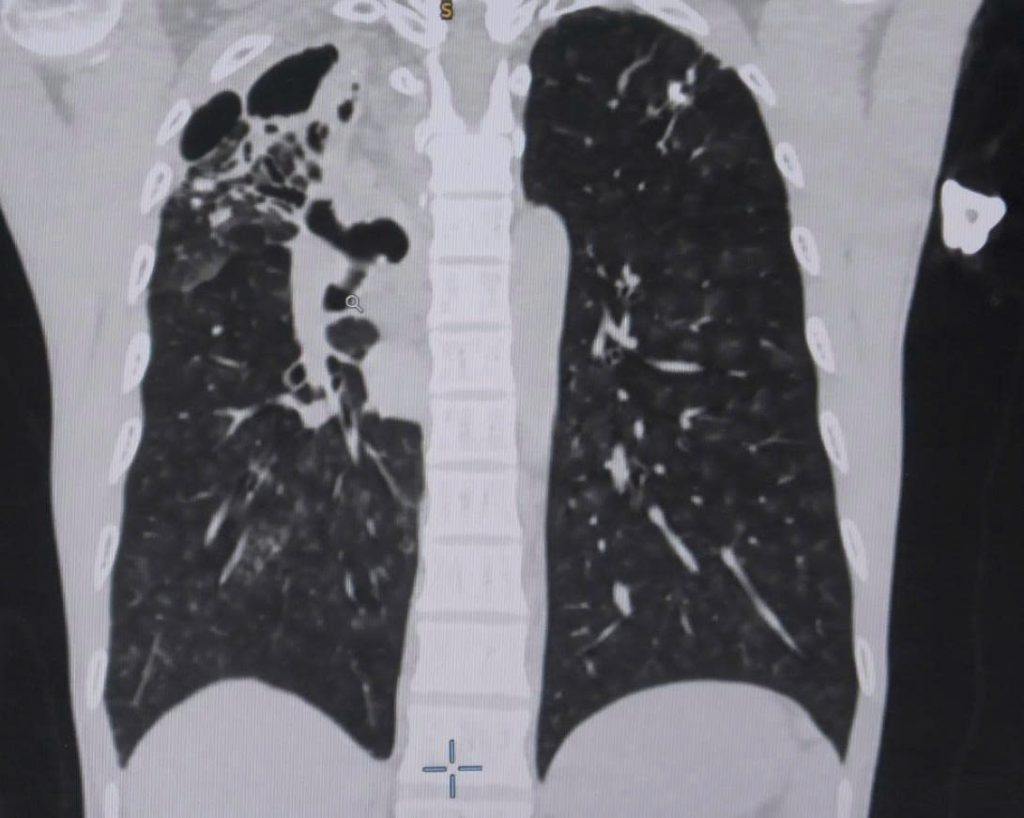

Tại đây, các bác sĩ đã chỉ định cho anh H. nội soi phế quản, chụp CT ngực có thuốc cản quang để đánh giá tình trạng bệnh lý phổi.

Kết quả ghi nhận phổi bên phải của anh H. có tình trạng hang lao cũ và có nhiều tổn thương giãn phế quản, phì đại động mạch phế quản. Đây là nguyên nhân của tình trạng vỡ mạch máu phế quản – một bệnh lý nguy hiểm có thể gây suy hô hấp dẫn đến đe dọa tính mạng, thậm chí khi máu tràn vào đường thở, bệnh nhân có thể ngạt thở ngay lập tức, chưa kể mất máu nhanh chóng.

Hình ảnh CT phổi cho thấy bệnh nhân bị vỡ mạch máu phế quản